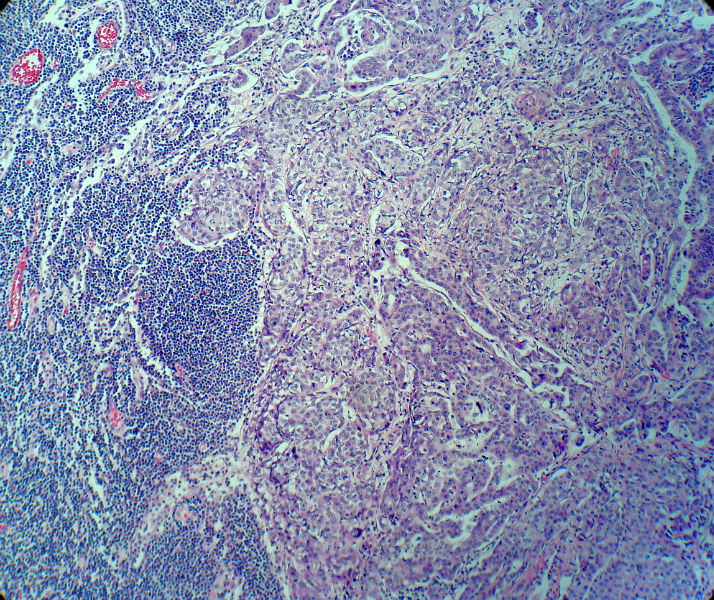

男,82岁,小肠穿孔紧急手术。

大体,小肠一段,长约60厘米,与粘膜面可见三个溃疡型肿物,肠系膜淋巴结肿大。

肿瘤呈巢片状分布,细胞大小相对一致,胞浆丰富,胞核呈细颗粒状,可见小核仁,血管较丰富,考虑神经内分泌肿瘤,加做免疫组化(Ki67、Syn、NSE、CgA、CD56)分级。

肠系膜淋巴结